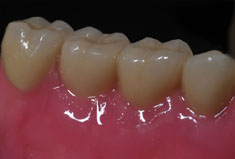

Fehlen in der Front oder im Seitenzahnbereich mehrere Zähne, ist eine Brücke oder Prothese vollkommen unnötig. Die fehlenden Zähne können entweder einzeln durch eine entsprechende Anzahl von Implantaten oder durch implantatgetragene festsitzende Brücken ersetzt werden. Das Bild der Kronen zeigt die drei Verschraubungen deutlich, im Mund liegen diese verdeckt am Gaumen oder im Bereich der Zunge.